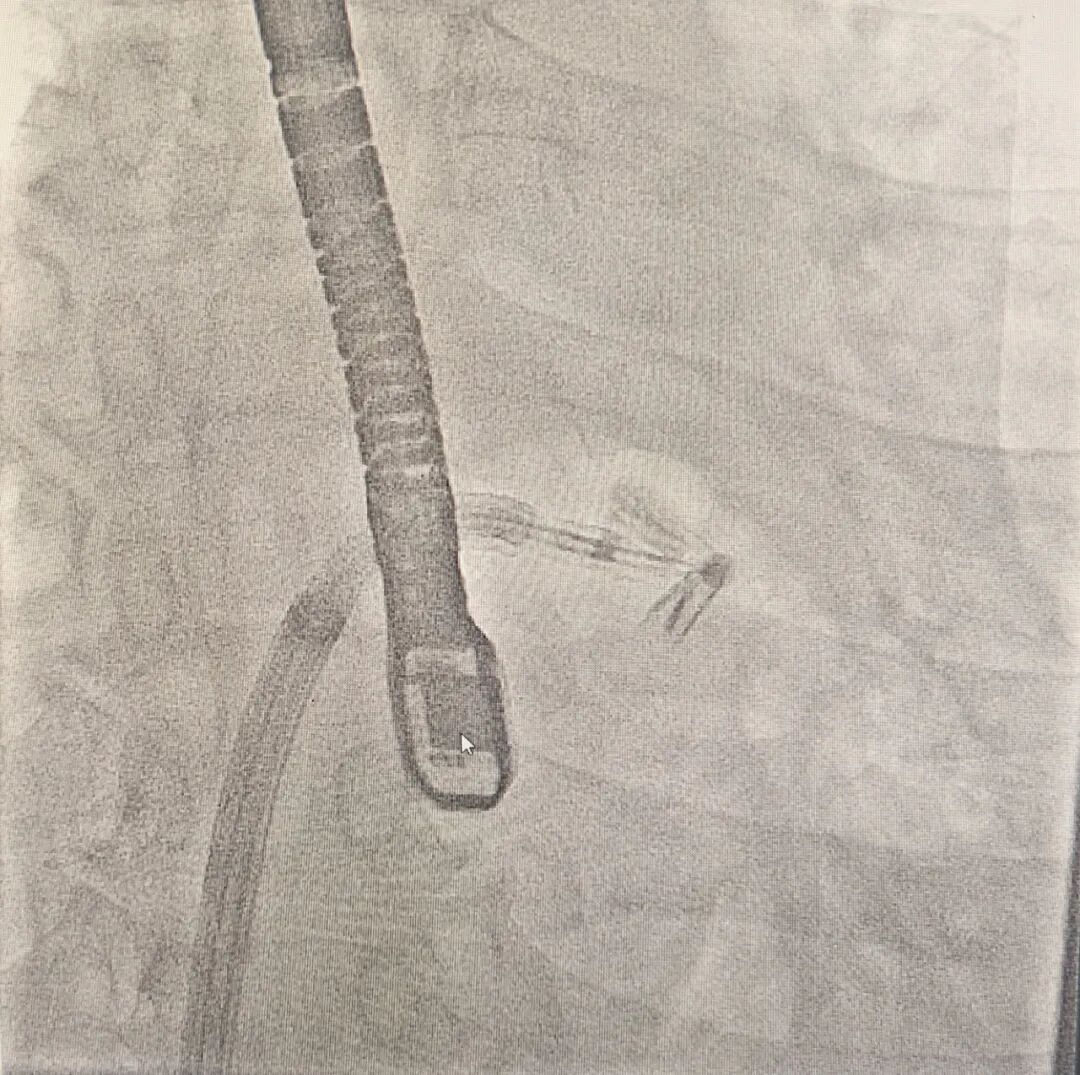

手术过程中,团队成功穿刺患者右侧股静脉,建立起通往心脏的微创路径。在经食道超声(TEE)的实时、立体导航下,精准穿刺房间隔,将导引导管稳稳送入左心房。接着,新型的NeoNova夹合系统沿导管被送入心脏,手术团队不断调整夹子的方向和角度,最终精准定位到二尖瓣前后瓣叶的中间及病变部位。术后,经食道超声反复确认夹持的稳定性及有效性,测定结果显示二尖瓣返流从中大量(3+)锐减至微量(1+),且平均跨瓣压差仅2mmHg,这表明在完美减少返流的同时,并未影响血液的正常通过。一场高难度的“心门”修复战宣告成功!